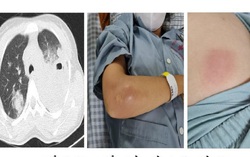

Phòng & chữa bệnh 08:33 13/10/2021Nữ bệnh nhân bị sưng đau ngực phải, sốt cao liên tục 40 - 41 độ C, khó thở, đã khám ở 3 cơ sở y tế nhưng không xác định được nguyên nhân. Tại BV, các bác sĩ chẩn đoán bệnh nhân bị nhiễm vi khuẩn ăn mòn cơ thể Whitmore.